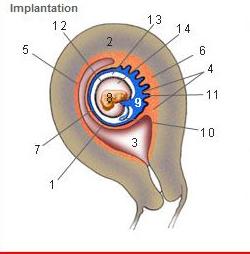

Where is the Desidua Capsularis?

1

Where is the Desidua basalis?

6

Where is the Desidua parietalis?

5

Where is the chorion frondosum?

11

Where is the amnion?

12

Where is the chorionic cavity?

13